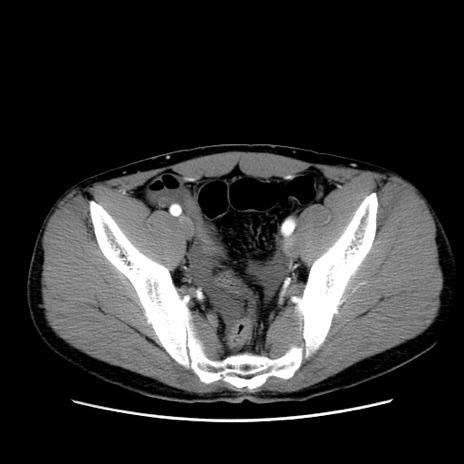

症例36(横断像)

【症例】20歳代 男性

【主訴】心窩部痛

【現病歴】今朝より上腹部痛あり。一旦軽快していたが再度出現したため救急要請。昨日夕に白身の魚を含む刺身を食べた。

【身体所見】BP 136/89mmHg、HR 74/min、BT 37.0℃、腹部:膨満、軟、心窩部に圧痛あり。反跳痛なし、筋性防御なし、腸雑音やや亢進あり。

【データ】WBC 17700、CRP 0.48